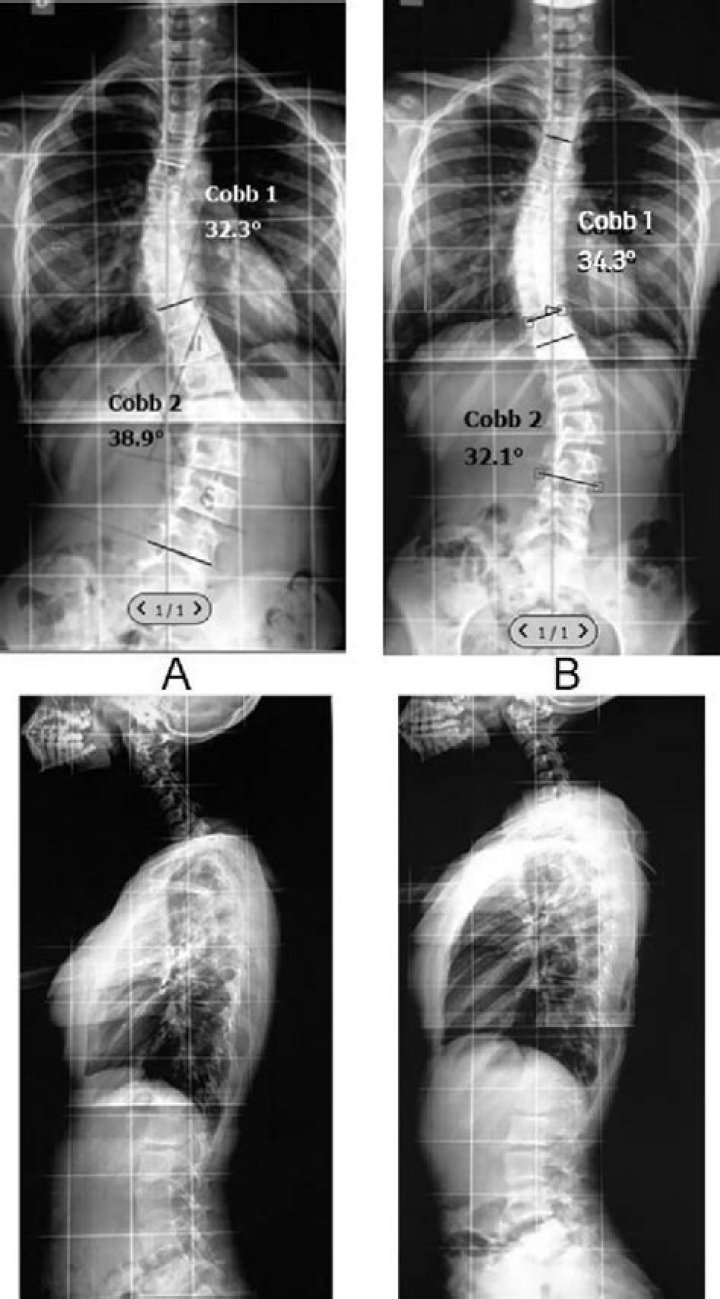

How is scoliosis degree calculated?

The Cobb angle is the most accepted method for measuring a scoliosis curvature. It's taken during a scoliosis X-ray and expresses the degree to which the spine bends, curves, and rotates away from a straight alignment. It's measured by finding the vertebrae (spinal bones) with the most tilt in each curve.